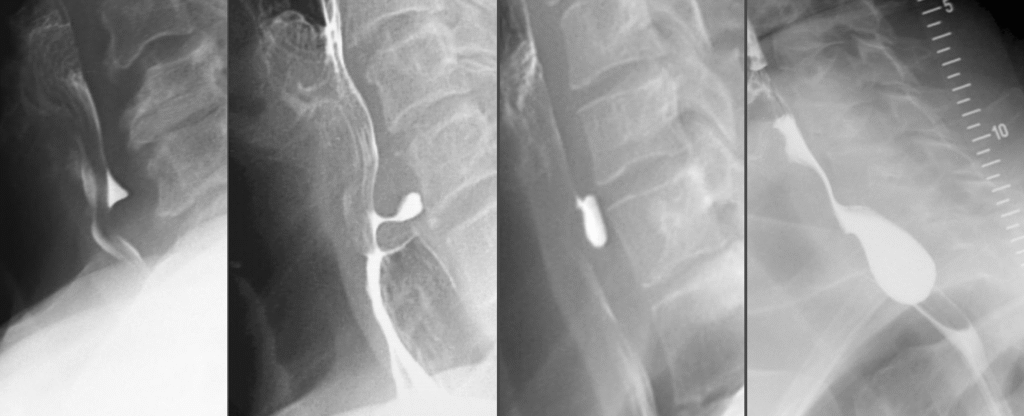

- Zenker-Divertikel (Pulsionsdivertikel, oben, Hypopharynx)

- Häufigstes Divertikel, meist ältere Männer

- Ursache: Muskelschwäche im Killian-Dreieck → Schleimhaut stülpt sich vor

- Klinik: Dysphagie, Regurgitation, gurgelnde Geräusche, Aspiration

- Diagnostik: Breischluck (KEINE Endoskopie – Perforationsgefahr!)

- Therapie: operative oder endoskopische Divertikulotomie

- Zenker-Divertikel = häufigstes, KEINE Endoskopie wegen Perforationsgefahr.